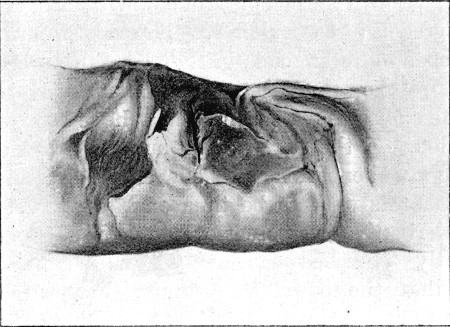

85. Lateral Incomplete Wound of Small Intestine. Slit Form416

86. Lateral Perforation of Small Intestine. Gutter Form417

87. Entry and Exit Wounds in a Transverse Perforation of Intestine418

88. Inner Aspect of Piece of Intestine Shown in Fig. 87419

89. Impaction of Omentum in Exit Wound of Abdominal Wall421